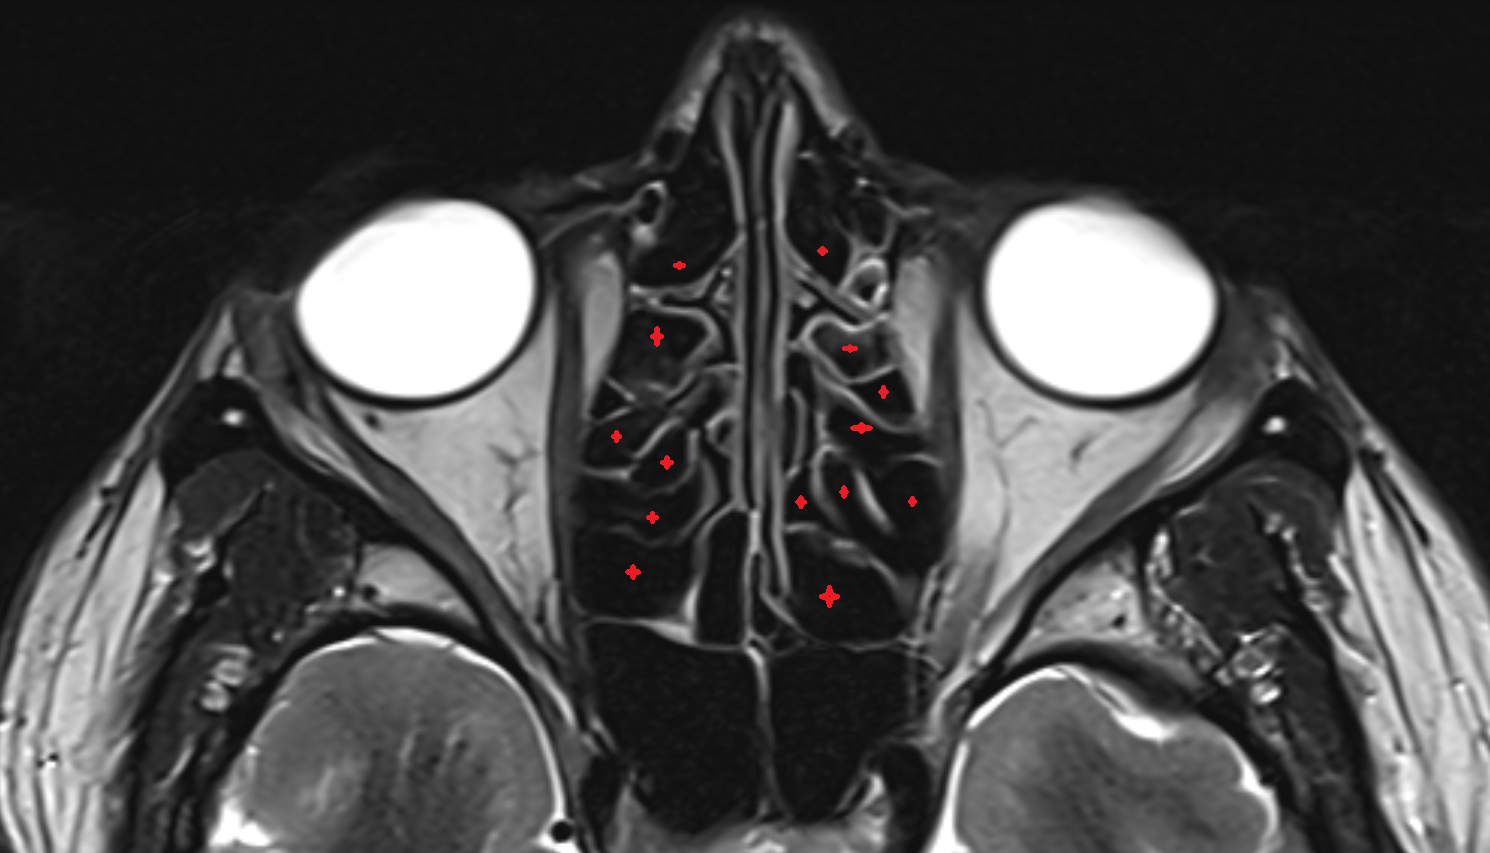

- Olfactory sulcus

- Common nasal meatus

- Inferior nasal concha

- Middle nasal concha

- Nasal septum

- Superior nasal concha